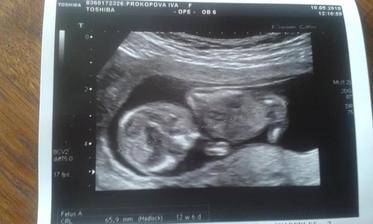

4.mimiko v bříšku 🙂

Po lednovém potratu k nám zavítal další andílek...Věřím, že tentokrát bude všechno v pořádku a k mým třem dětičkám přibude parťák do